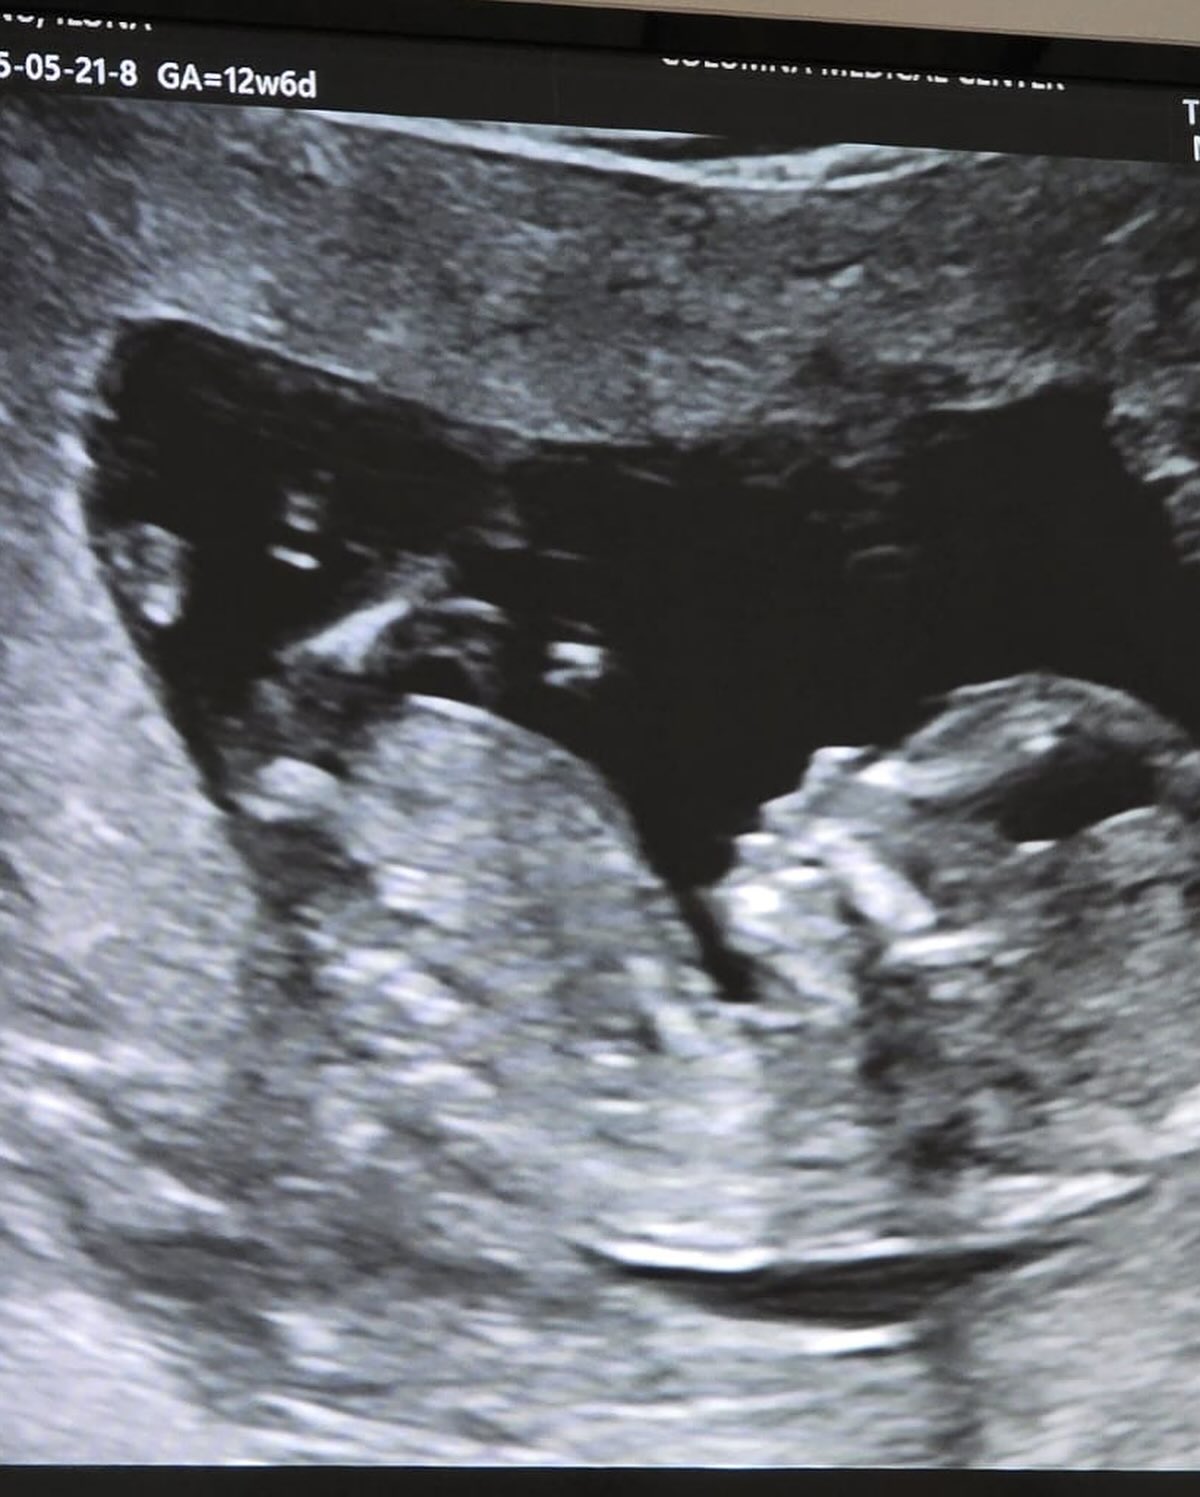

Vestea sarcinii, Ilona Brezoianu a dat-o în stilul caracteristic, folosindu-se din plin de umor. Aceasta și-a anunțat fanii că în familia ei va apărea un nou membru „tot cu nasul mare”. Mai mult, pentru ca nimeni să nu creadă că este vorba despre o glumă, actrița a împărtășit în mediul online și prima ecografie.

„Eu și Andrei avem nasurile mari și o să facem un copil tot cu nasul mare. Până una alta e foarte drăguț și noi suntem mega fericiți! V-am pus și o poză cu el ca să mă credeți pe cuvânt. Acum puteți să vă continuați treburile”, a scris Ilona Brezoianu, în mediul online.